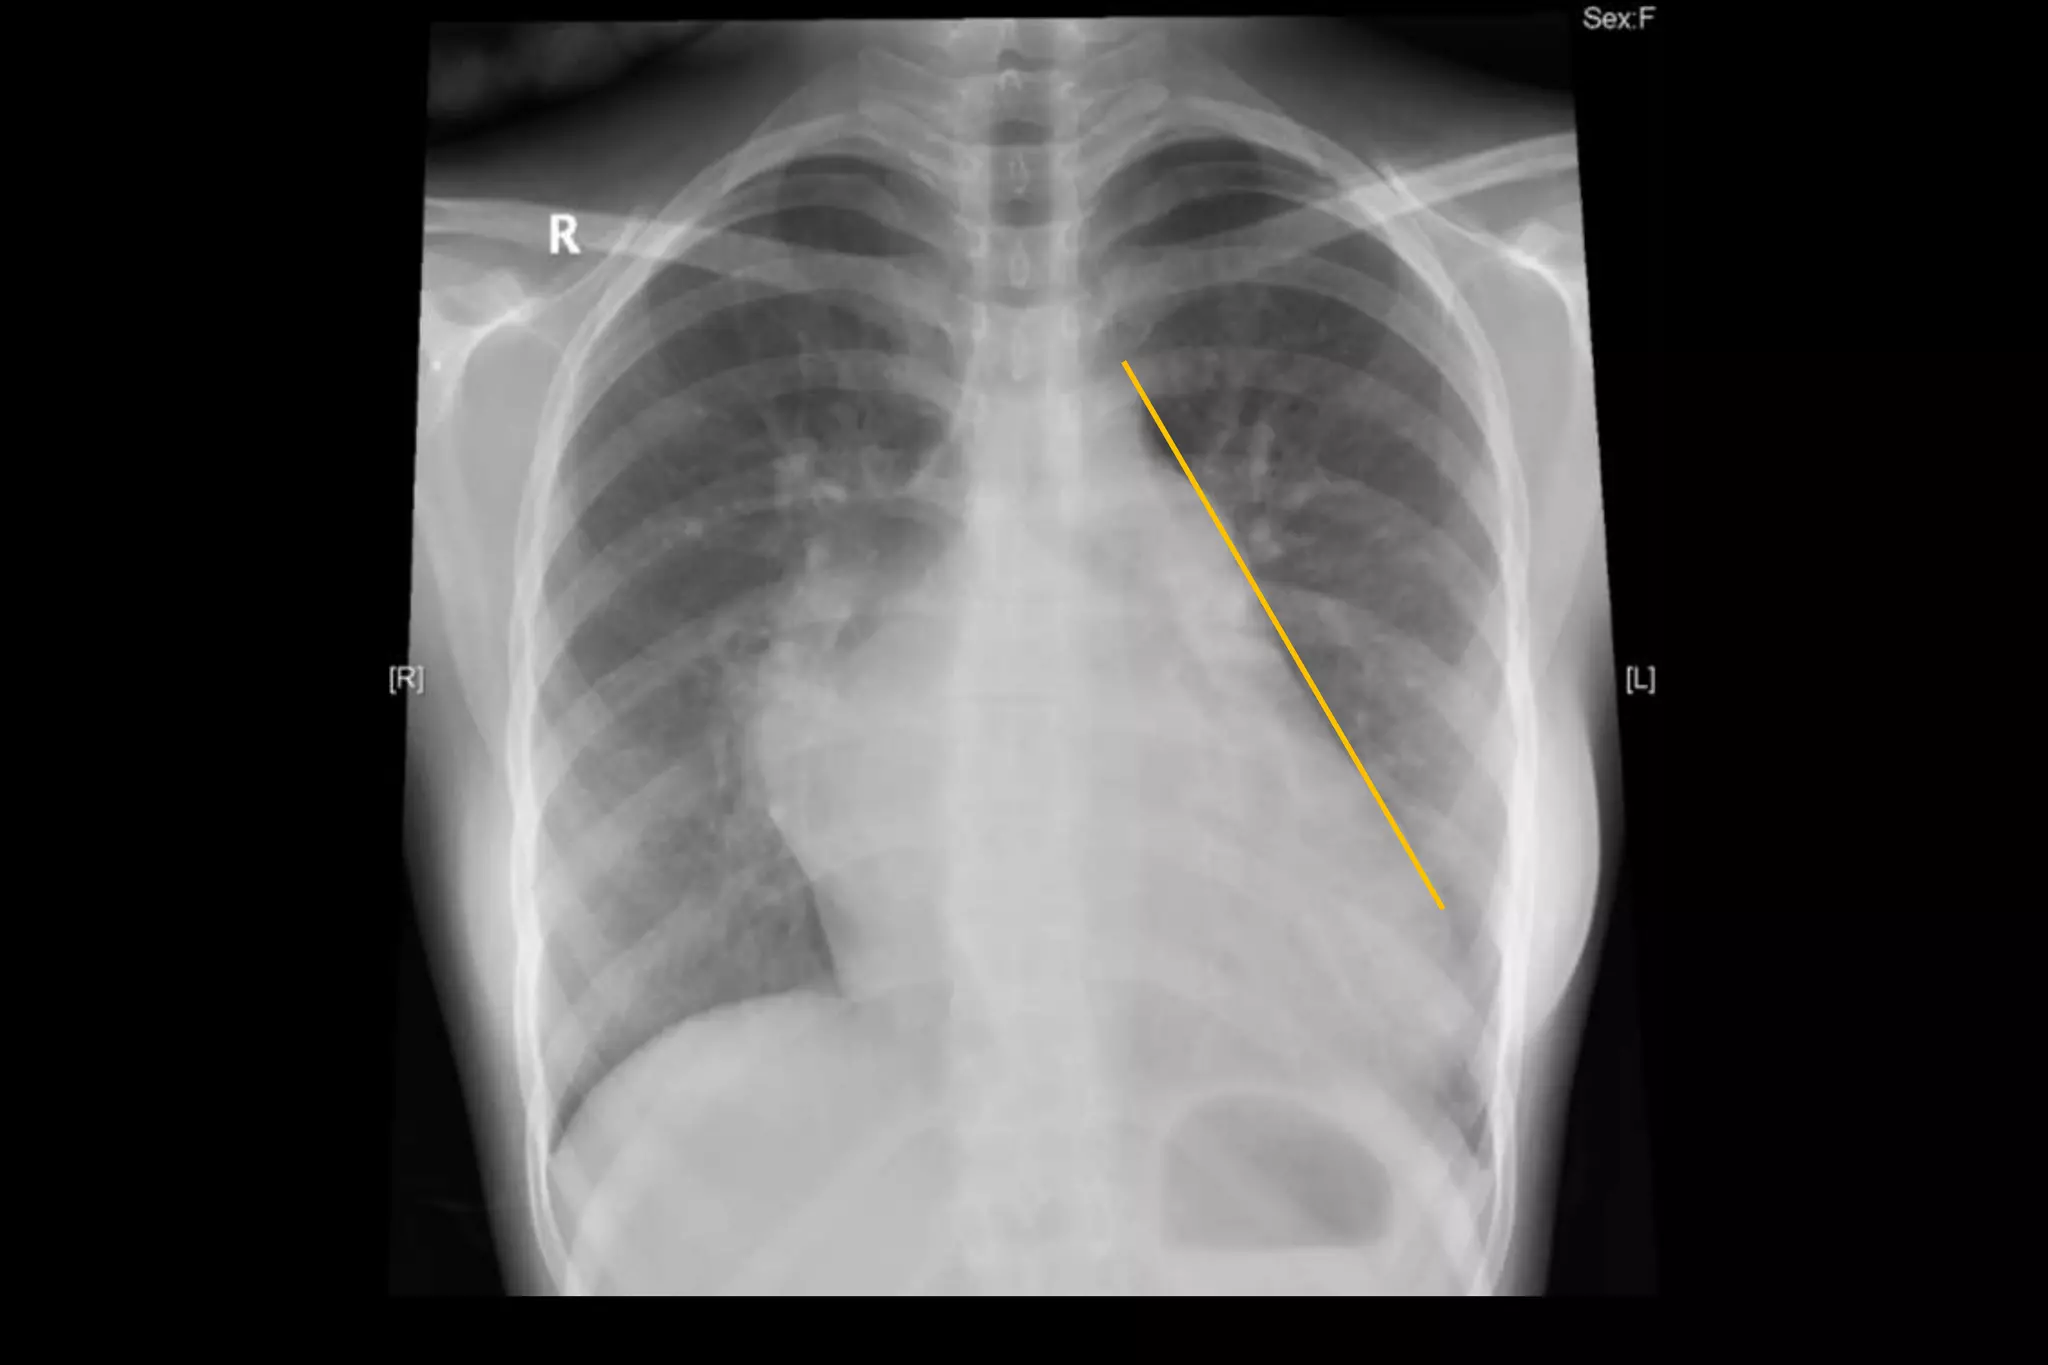

MITRAL REGURGITATION ECG CHEST XRAY PPT Free Download

Mitral Regurgitation Chest X ray Wikidoc